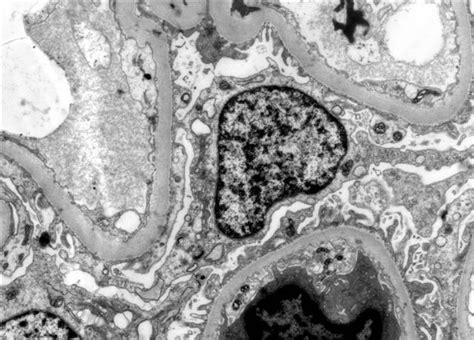

Norint apsisaugoti nuo vėjaraupių rekomenduojama paskiepyti visus anksčiau nesirgusius vaikus. Ypač patartina skiepyti lankančius darželius bei mokyklas. Dažniausiai rekomenduojama skiepyti vėjaraupių vakcina kartu su tymų, parotitinės infekcijos ir raudonukės (MMR) vakcina. „Varilrix“ gyvoji vakcina naudojama sveikų, vėjaraupiais nesirgusių, 9 mėnesių ir vyresnių vaikų bei suaugusiųjų skiepams nuo vėjaraupių. Ji padeda organizmui pasigaminti antikūnų, kurie apsaugo nuo minėtos ligos. „Varilrix“ švirkščiama į poodį, kaskart į kitą vietą. Jos veiklioji medžiaga yra gyvas susilpnintas „Varicella Zoster Oka“ padermės virusas, išaugintas žmogaus diploidinių ląstelių MRC-5 kultūroje.